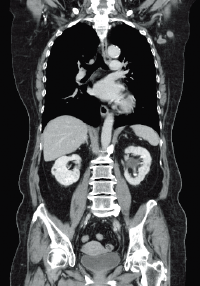

Thoracoabdominal scanning